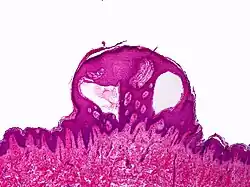

Lymphangioma circumscriptum; only stratum papillare is affected.

A biopsy of the affected skin and histological examination under a microscope are necessary to confirm the diagnosis of lymphangioma circumscriptum.